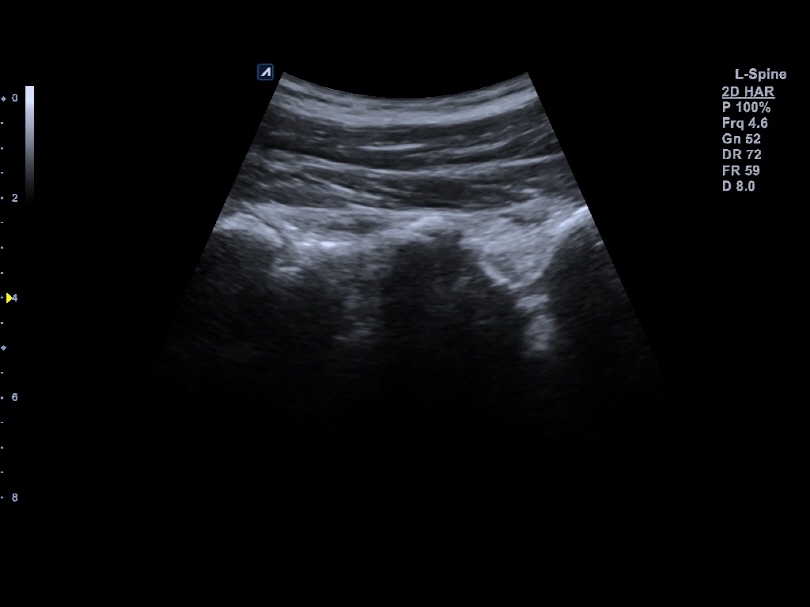

C1-6CT

C-Architecture (PowerView™)

Convex transducer (1-6MHz)

Application:

Abdomen, EM, Gynecology, Obstetrics